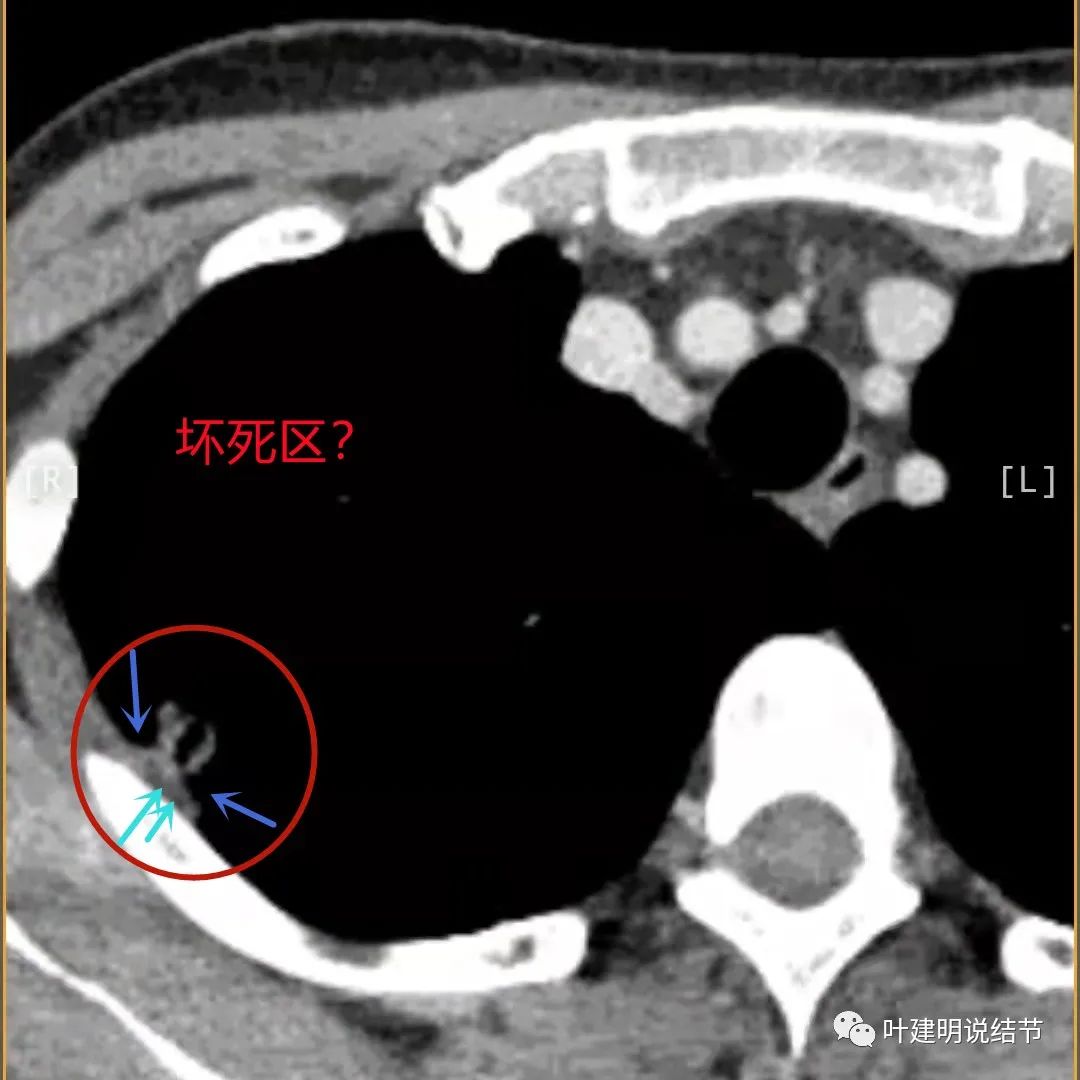

蓝色箭头所指处居然有低密度影,难道是坏死?因为比肌肉密度低,也无强化,况且主病灶的中间也有个低密度的小点状

此层也见明显的低密度区域(天蓝色箭头)

胸膜处明显增厚伴低密度区域

天蓝色箭头示病灶低密度区,考虑坏死可能性大,桔色箭头示边缘凹陷无膨胀性

上图示空洞偏心,而且红色箭头所指处与空腔似乎是整合,而非囊壁生长增厚。天蓝色箭头示近胸膜处的低密度区域,考虑坏死成分,囊壁的邻近部分也是极低密度区域,也可能是干酪样坏死区

薄层影像印象:病灶有明显强化,且邻近胸膜处及部分囊壁区有极低密度区域,考虑干酪样坏死可能性大,肿瘤的坏死可能性小,肿瘤一般要长的比较大,中央缺血性坏死。整体病灶也是觉得散,且邻近胸膜处甚厚。考虑炎性,尤其是肉芽肿性炎伴干酪样坏死可能性大。